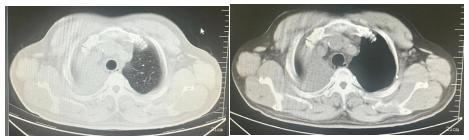

据了解,58岁的高先生于1个月前出现咳嗽、咳痰伴痰中带血症状,完善胸部CT检查显示右肺上叶肿物并伴有肺不张,与右主气管关系密切。于医院行电子支气管镜检查以及组织活检,病理提示:肺鳞状细胞癌。多方问诊,得到的答案让家人备受打击,于是慕名找到哈医大四院松北院区胸外科张凯副主任。结合病理类型以及患者年龄、身体状况等因素,张凯副主任为患者制定了手术方案:右肺上叶肺癌袖式切除术,让患者和家属看到了希望。